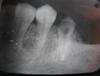

Nadzivany Опубликовано 21 августа, 2013 Поделиться Опубликовано 21 августа, 2013 (изменено) Добрый день! Зафиксировал шкв и временную коронку. Пациентка пришла через 3 месяца, я снял временную коронку и вот что увидел... Уступ был придесневой. Зуб был ранее лечен по поводу пульпита. На снимке с эндодонтией все ок. У кого была такая ситуация? В чем причина? За качество снимков прошу извинить... Изменено 21 августа, 2013 пользователем Nadzivany Ссылка на комментарий

Чертков Александр Опубликовано 21 августа, 2013 Поделиться Опубликовано 21 августа, 2013 Рентген до - после эндо можно? Похоже на цервикальную резорбцию. Времяшка и преп "добили". Просто так такие переломы не возникают. По тактике - на выход. С Уважением Ссылка на комментарий

Чертков Александр Опубликовано 21 августа, 2013 Поделиться Опубликовано 21 августа, 2013 (изменено) Не претендуя на истину хочу сказать что действительно похоже на резорбцию. И, я бы удалил этот зуб без всяких вмешательств... Деструкция на уровне альвеолы...значит нужно удлинение коронки, удлинение приводит к нарушению соотношения коронка - корень. Что планируете в зоне 6, 7 зубов ? С Уважением Изменено 21 августа, 2013 пользователем Чертков Александр 1 Ссылка на комментарий